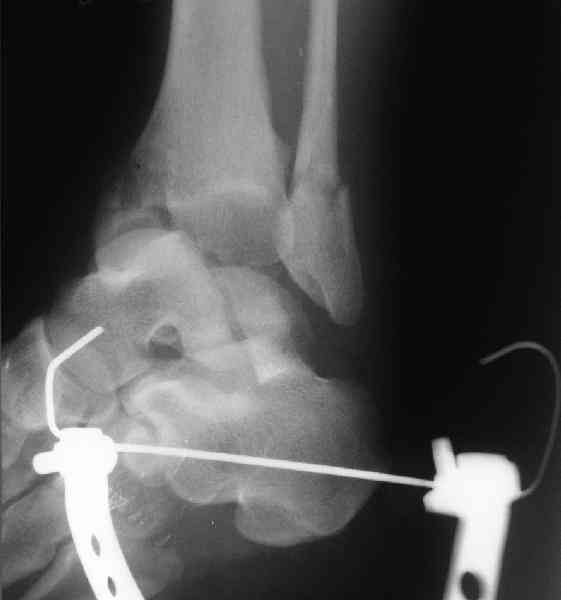

повторили рентгенограммы и доделали проекции, к единому мнению все еще не пришли

На ренгенограмме не уловил многоскольчатость тарана, чтобы доказать, конечно, можно было исследовать на КТ, потом КТ дает ориентацию фрагментов.

Два фрагмента суставной поверхности тарана можно восстановить боковой компрессией шурупами и дополнительно костная пластика.

Наружный фиксатор "голень-пятка", "лигаментотаксис" при поступлении, домой через 48 часов после обучения ходьбы на костылях, в течение ближайшего времени осмотр в поликлинике для определения кондиции мягких ткани (тест на образование морщин в зоне разреза), при отсутствии отека примерно на 6-7 день с момента травмы операция.